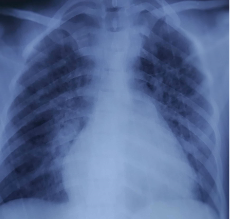

A male patient aged 23, on automated peritoneal dialysis since 2021 (APD: total volume 10 L, 4 cycles of 2 h, injection volume 2 L, final stasis 1 L, concentrations 2.27%). The measured dialysis dose was a total Kt/V of 1.35 and a WCCr of 38 L/week/1.73 m2, nPCR at 0.85. One week prior to admission, the patient presented with non-radiating retrosternal chest pain with dyspnea. An ECG and chest X-ray were performed, which came back unremarkable. With worsening chest pain and dyspnea, the patient was admitted to the emergency department. Clinical examination revealed tachycardia at 115 bpm, BP 140/90 mmHg, apyrexia, decreased heart sounds, orthopnea, SpO2 of 95% on room air, no crepitus rales, and no signs of right heart failure. ECG showed diffuse microvoltage. Chest X-ray revealed cardiomegaly (ICT 0.7) with hilar overload (Figure 3.). TTE showed a large circumferential pericardial effusion at 23 mm without collapse, with fibrin deposits, dilated IVC, and 50% LVEF (Figure 4.). A biological inflammatory syndrome was present, with CRP of 160 mg/L without hyperleukocytosis, and negative troponin 28 ng/dL. The patient underwent emergency pericardiocentesis, yielding 500 mL of hematic, exudate fluid (protein 56 g/L). Cytobacteriological examination, BK testing, and GeneXpert in the puncture fluid were negative, with no cells suspected of malignancy on pathology.

Figure 3.Chest X-ray showing cardiomegaly (ICT 0.7) with hilar overload